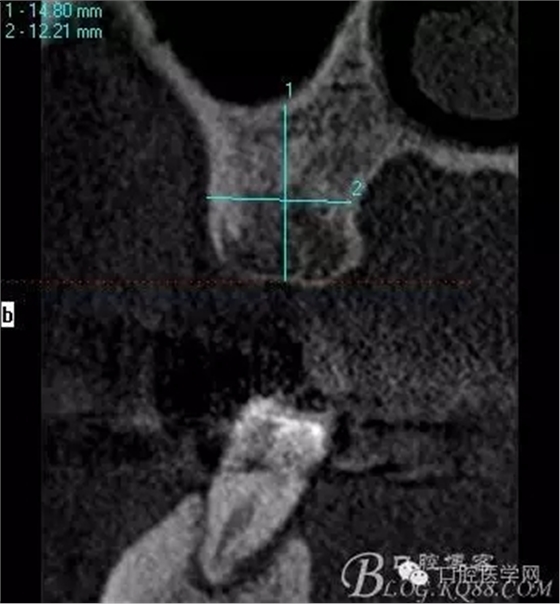

植入當(dāng)然毫無難度可言,只是想術(shù)后的方向更加賞心悅目而已,14稍微有點難度,記住 上頜牙顎側(cè)骨板肯定比頰側(cè)硬多了。 所以(特別是柱行種植體柱行鉆)永遠要記住上頜牙備洞過程是會往頰側(cè)慢慢偏出去的 。(根型植體菱形鉆相對這個問題好控制點)所以我們第一鉆定位要比預(yù)計的中心點更加靠顎側(cè)多點 ,到底多多少,這個很難把握,感覺吧 。 上圖我畫了小圈的地方,是種植體離頰側(cè)和近中骨壁的距離空腔 (這個情況可以考慮植骨或者不植骨 我選擇了自體骨)。

頰顎向的方向也很理想 箭頭所示 空間填滿了自體骨